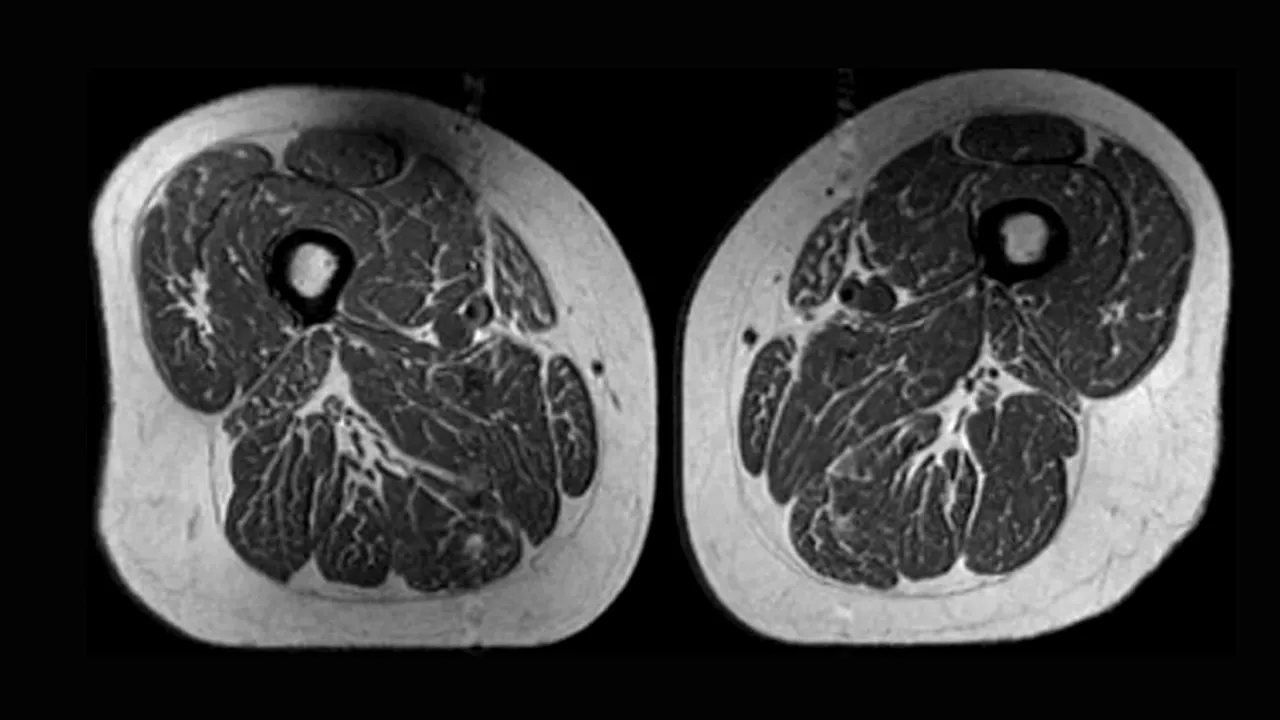

O scanare RMN a coapselor unei femei. Dieta ei era în proporție de 87% ultraprocesată. Sursa foto: Radiological Society of North America

Analiza, bazată pe scanări RMN realizate pe peste 600 de persoane, arată o legătură clară între consumul de alimente ultraprocesate și creșterea grăsimii intramusculare. În unele cazuri, imaginile au relevat mușchi cu un aspect comparat de specialiști cu cel al unei „fripturi marmorate”, din cauza straturilor fine de grăsime infiltrate între fibrele musculare. Cercetătorii au observat că acest fenomen apare chiar și la persoane care nu prezentau semne de osteoartrită, sugerând că degradarea calității musculare începe înainte de apariția simptomelor, scrie CNN.